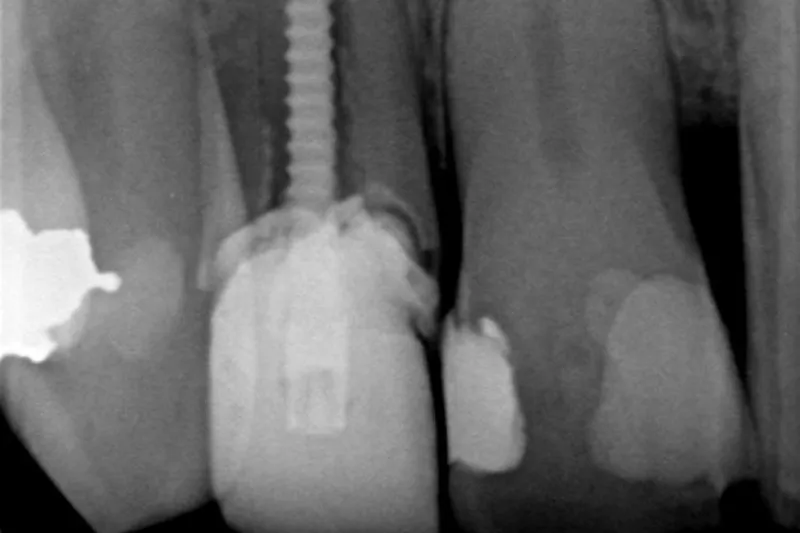

Ved logistisk regressionsanalyse fandt man, at en række faktorer havde signifikant sammenhæng med tandtabet. Fx patientens alder (OR for patient > 75 år var 2,2; P < 0,001), og tandtypen (OR for underkæbemolar var 2,0; P < 0,001. For overkæbemolar var OR 1,9; P < 0,001). Mest åbenlys var dog sammenhængen med den restaurative behandling, tænderne havde fået efter rodbehandlingen.

Sammenlignet med en indirekte koronal restaurering og støbt stiftopbygning var risikoen for tandtab lidt mere end tre gange højere både ved tænder uden restaurering (OR = 3,2; P < 0,001) og ved tænder med plastfyldning og direkte stiftopbygning (OR = 3,2; P < 0,001). For tænder med plastkrone uden opbygning var OR 2,2 (P < 0,001).